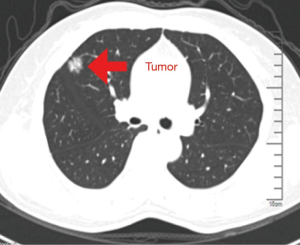

A 55-year-old female was admitted to our hospital. CT scan revealed a nodule in the anterior segment of the right upper lobe with superficial lobulated lesion and short burr-like boundaries (Figure 1). Because of the small size and placement of the lesion, peripheral nodule in the right-upper-lobe, the patient received a uniportal VATS resection with non-intubated anesthesia (Figure 2).

The chest computed tomography (CT) indicated a circular-like nodule about 1.8 cm × 1.6 cm in the anterior segment of the right upper lobe; the lesion had uneven density, superficial lobulated lesion and short burr-like boundaries. In addition, small dot-like nodules were seen around the lesion. There was no stenosis or expansion of the trachea and bronchus nor were there enlarged mediastinal lymph nodes. Enhanced cranial magnetic resonance imaging (MRI), general bone scanning, and enhanced abdominal CT showed no evidence of tumor metastasis. The patient’s preoperative diagnosis was lung cancer of the right-upper-lobe, T1aN0M0, phase IA. The results of pulmonary function test were quite satisfactory: forced expiratory volume in 1 second (FEV1) was 1.89−89%. The cardiac function test showed aortic and mitral regurgitation (mild) and diastolic insufficiency, ejection fraction (EF): 72%. The systolic function of the left ventricle was normal.